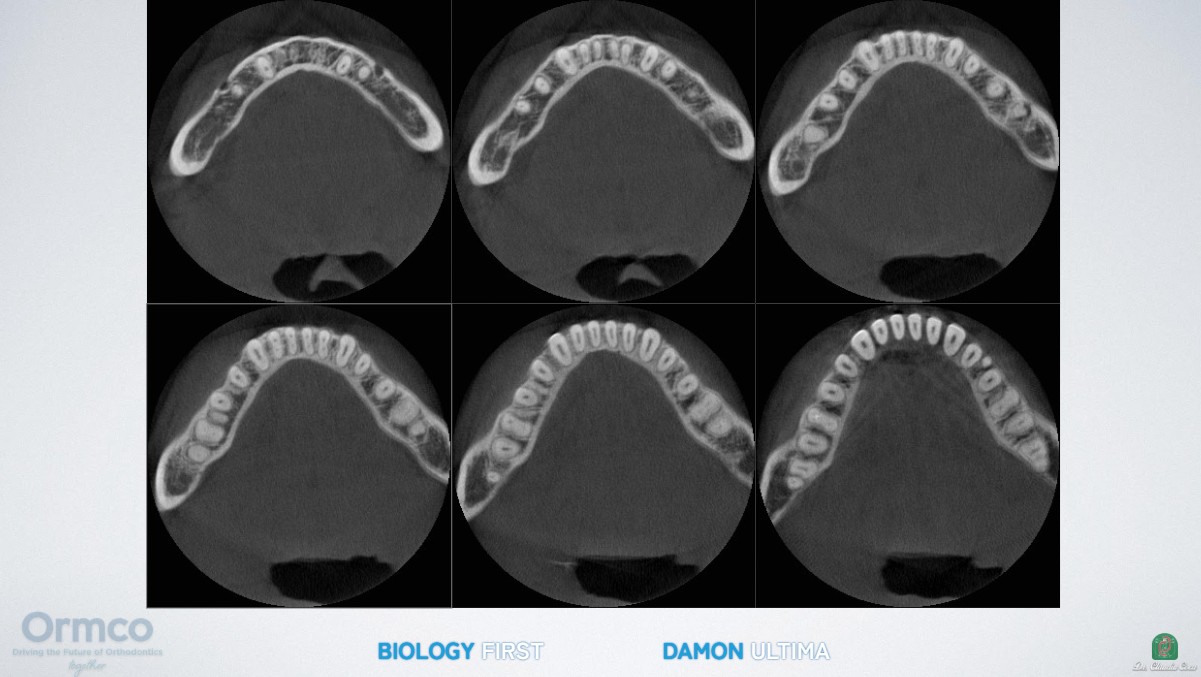

Orthodontic tooth movement is fundamentally a process of alveolar bone remodeling driven by low-force, low-friction biomechanics (pressure-tension theory: osteoclast activity on the pressure side and osteoblast activity on the tension side).¹

The Damon Ultima passive self-ligating system, used properly with actual low forces, allows teeth to move through bone in a more physiological manner without the need for heavy mechanics. At the same time, the functional matrix of the masticatory muscles is respected.

Patient-Specific Archform Generated by Function

A distinctive feature of the Damon Philosophy is that the final archform is unique to each patient—it is generated by function and the patient’s own biology rather than being decided by mathematical formulas (as in classical orthodontics) or by tooth-driven mechanics (as in aligners).